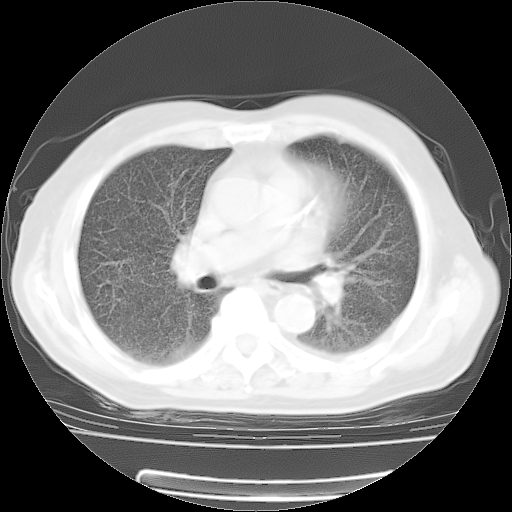

4月14日肺部CT

肺部CT平扫未见异常。